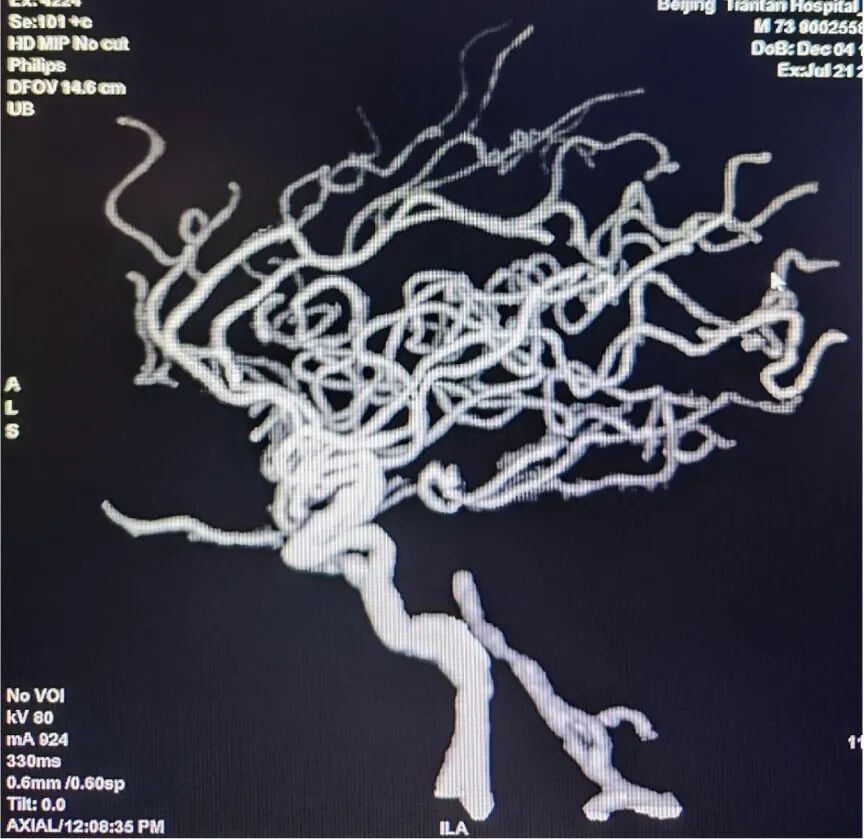

术后影像

狭窄改善明显,前向血流维持良好,mTICI分级3级

该患者为原位狭窄,导丝导管通过困难,通路的顺利建立是本例病患手术成功的关键因素。

Locaste长鞘头端柔软,近端支撑力强。Skathi远端通路导管支撑力足够,系统稳定,操作顺畅,通过性好,远端亲水头手感丝滑,裸奔直接通过V3-4段,到达基底动脉狭窄近段轻松自如。狭窄部位狭窄程度较重,通过困难,逐步球扩后置入支架,Skathi远端通路导管极其稳定,通过球囊、支架系统顺利,可为进一步的安全治疗奠定基础。